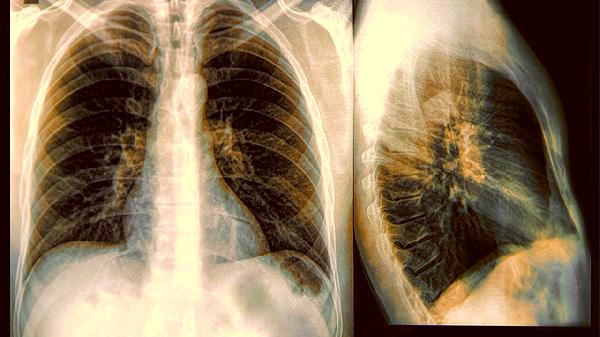

2.呼吸系统的异常表现

当感染波及肺部时,会出现铁锈色痰或胸痛。CT检查可能显示"磨玻璃影",这是免疫系统正在和病原体激烈交火的证据。